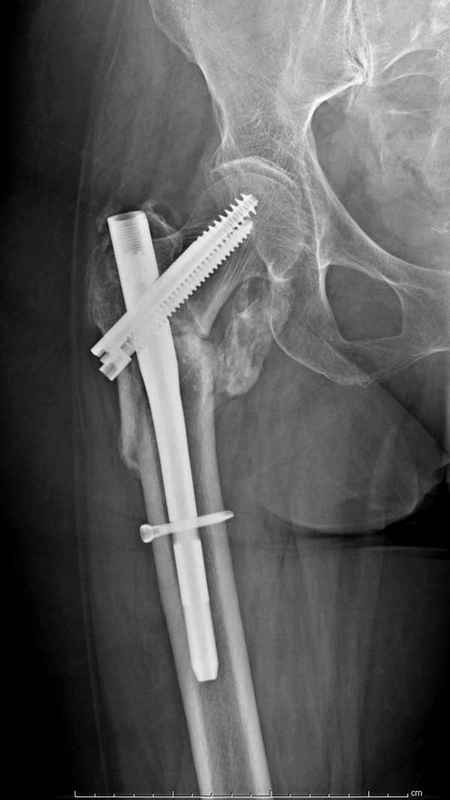

Здесь 83 года, травма в результате падения

Djoldas Kuldjanov, M.D.

Department of Orthopedic Surgery

St. Louis University